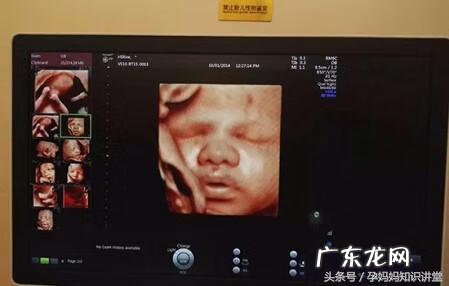

文章插图